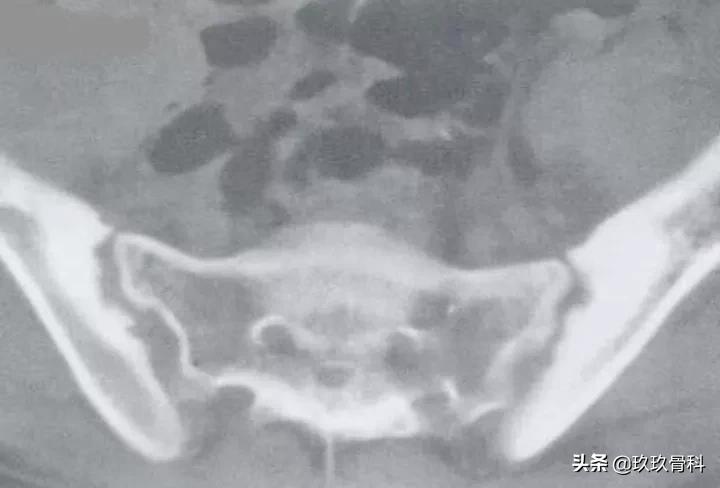

强直性脊柱炎(Ⅳ级)

图注:双侧骶髂关节骨质破坏,关节间隙消失,骨性强直。双侧髋关节面侵蚀,轮廓粗糙不光滑,以髋臼明显,骨盆疏松。

图注:CT示双侧骶髂关节破坏,多发小囊变,关节间隙消失,骨性强直,骨质疏松。